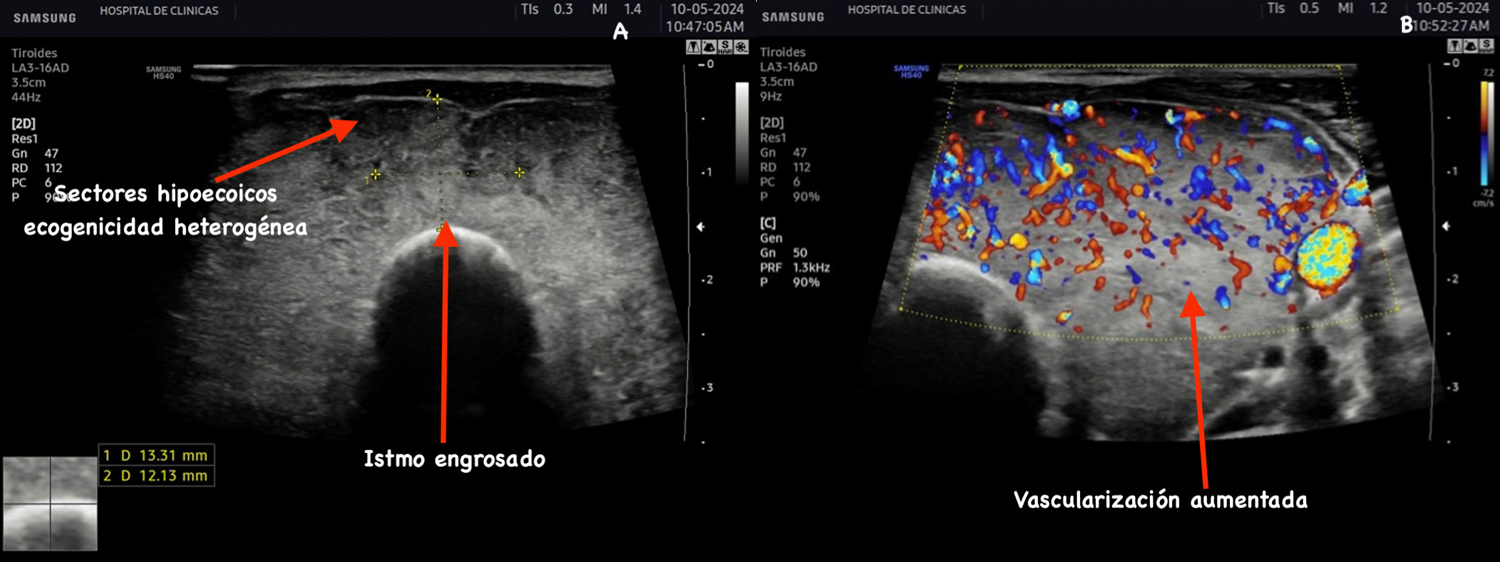

Bocio tóxico difuso (EGB)

Definimos bocio como el aumento de volumen de la glándula tiroides, se considera un volumen glandular normal hasta 12 cc según diferentes autores.

Es la causa más común de hipertiroidismo, con una

prevalencia entre 0,4 a 1% de la población6. Es más frecuente

en el sexo femenino. Se caracteriza por un exceso de

producción de hormonas tiroideas de etiología autoinmune7.

Por lo general, se acompaña de un agrandamiento de la

tiroides (bocio), con desplazamiento de las estructuras

vasculares del cuello lateral y/o dorsalmente, como

resultado del aumento de tamaño de los lóbulos tiroideos.

Protrusión de las superficies anteriores de los lóbulos,

agrandamiento del istmo, redondeo del contorno angular

normal. Disminución difusa de la ecogenicidad. Aumento

de la vascularización significativa del parénquima de

forma simétrica (Figura 5)7.

La hipoecogenicidad observada en la enfermedad de Graves se debe a la hipertrofia e hiperplasia de la células foliculares e infiltrado linfocitario, disminución del contenido de coloide en los folículos y aumento de la vascularización como se observa en la figura 56.

Figura 5: Corte transversal y longitudinal de tiroides de paciente con EGB. Se señala el itsmo engrosado, disminución de la ecogenicidad, estructura

heterogénea, aumento de la vascularización del parénquima.